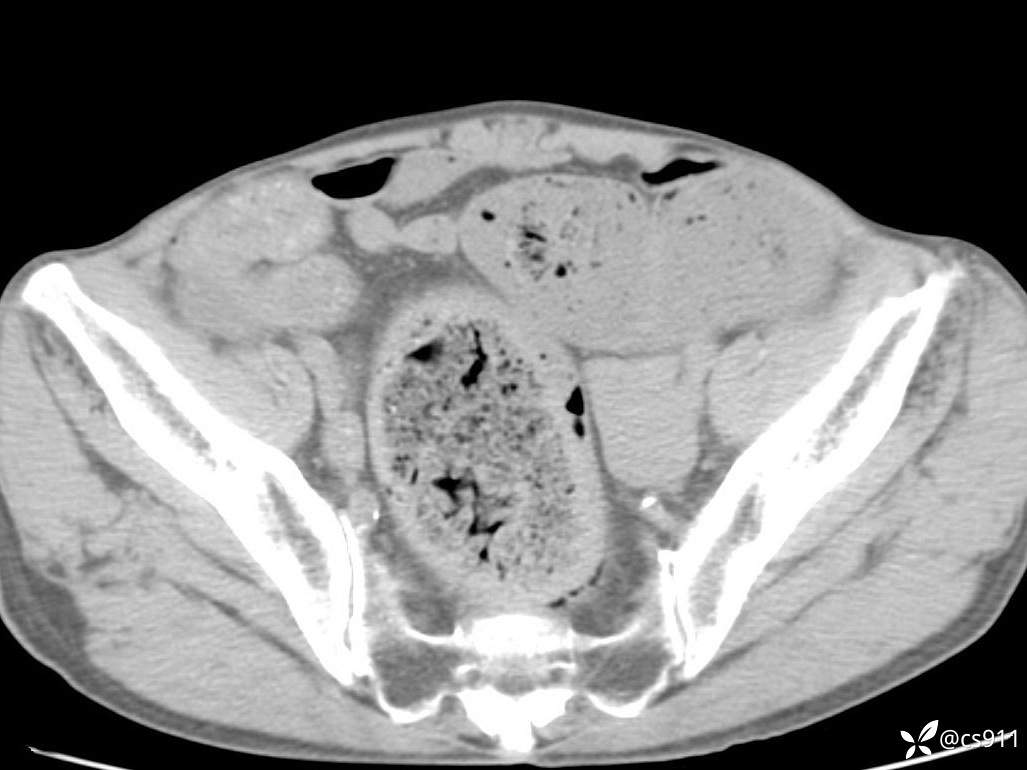

急腹症之急诊CT,原因?答案公布

男,77岁,腹痛、腹胀伴恶心呕吐1天。呕吐胃内容物,非喷射性呕吐,有咖啡色样胃内容物,诉有胃穿孔病史。查体:全腹平,下腹部压痛,全腹无反跳痛,叩诊呈浊音,移动性浊音阴性,肠鸣音减弱,1-2次/分。肛检:直肠未扪及明显肿物,可触及大量粪块。

血淀粉酶(AMY) HH 1859 U/L 35-135

癌胚抗原(CEA) H 27.44 ng/ml 0-5